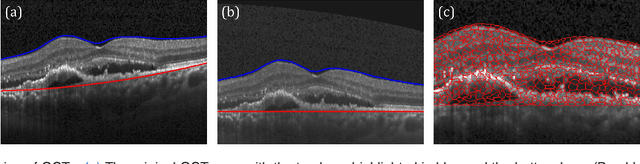

Abstract:Diagnosis and treatment guidance are aided by detecting relevant biomarkers in medical images. Although supervised deep learning can perform accurate segmentation of pathological areas, it is limited by requiring a-priori definitions of these regions, large-scale annotations, and a representative patient cohort in the training set. In contrast, anomaly detection is not limited to specific definitions of pathologies and allows for training on healthy samples without annotation. Anomalous regions can then serve as candidates for biomarker discovery. Knowledge about normal anatomical structure brings implicit information for detecting anomalies. We propose to take advantage of this property using bayesian deep learning, based on the assumption that epistemic uncertainties will correlate with anatomical deviations from a normal training set. A Bayesian U-Net is trained on a well-defined healthy environment using weak labels of healthy anatomy produced by existing methods. At test time, we capture epistemic uncertainty estimates of our model using Monte Carlo dropout. A novel post-processing technique is then applied to exploit these estimates and transfer their layered appearance to smooth blob-shaped segmentations of the anomalies. We experimentally validated this approach in retinal optical coherence tomography (OCT) images, using weak labels of retinal layers. Our method achieved a Dice index of 0.789 in an independent anomaly test set of age-related macular degeneration (AMD) cases. The resulting segmentations allowed very high accuracy for separating healthy and diseased cases with late wet AMD, dry geographic atrophy (GA), diabetic macular edema (DME) and retinal vein occlusion (RVO). Finally, we qualitatively observed that our approach can also detect other deviations in normal scans such as cut edge artifacts.

Abstract:The identification and quantification of markers in medical images is critical for diagnosis, prognosis, and disease management. Supervised machine learning enables the detection and exploitation of findings that are known a priori after annotation of training examples by experts. However, supervision does not scale well, due to the amount of necessary training examples, and the limitation of the marker vocabulary to known entities. In this proof-of-concept study, we propose unsupervised identification of anomalies as candidates for markers in retinal Optical Coherence Tomography (OCT) imaging data without a constraint to a priori definitions. We identify and categorize marker candidates occurring frequently in the data, and demonstrate that these markers show predictive value in the task of detecting disease. A careful qualitative analysis of the identified data driven markers reveals how their quantifiable occurrence aligns with our current understanding of disease course, in early- and late age-related macular degeneration (AMD) patients. A multi-scale deep denoising autoencoder is trained on healthy images, and a one-class support vector machine identifies anomalies in new data. Clustering in the anomalies identifies stable categories. Using these markers to classify healthy-, early AMD- and late AMD cases yields an accuracy of 81.40%. In a second binary classification experiment on a publicly available data set (healthy vs. intermediate AMD) the model achieves an area under the ROC curve of 0.944.

Abstract:The identification and quantification of markers in medical images is critical for diagnosis, prognosis and management of patients in clinical practice. Supervised- or weakly supervised training enables the detection of findings that are known a priori. It does not scale well, and a priori definition limits the vocabulary of markers to known entities reducing the accuracy of diagnosis and prognosis. Here, we propose the identification of anomalies in large-scale medical imaging data using healthy examples as a reference. We detect and categorize candidates for anomaly findings untypical for the observed data. A deep convolutional autoencoder is trained on healthy retinal images. The learned model generates a new feature representation, and the distribution of healthy retinal patches is estimated by a one-class support vector machine. Results demonstrate that we can identify pathologic regions in images without using expert annotations. A subsequent clustering categorizes findings into clinically meaningful classes. In addition the learned features outperform standard embedding approaches in a classification task.